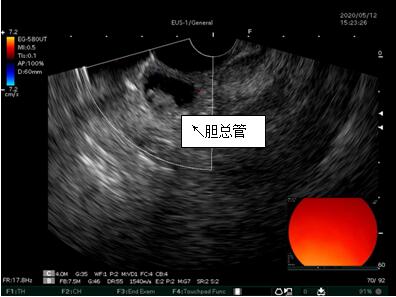

69歲王姓患者,因“發(fā)現(xiàn)無痛性黃疸1月”入院,根據(jù)患者病史,患者診斷傾向于壺腹部腫瘤所致梗阻性黃疸。予以完善腹部CT及上腹部MRI加MRCP均顯示肝內外膽管擴張,未發(fā)現(xiàn)明顯膽管,胰腺及十二指腸乳頭部腫瘤,且患者CA199正常。以前醫(yī)院未引進超聲內鏡,這類患者到此就遇到診斷瓶頸。此患者經過消化內科張丹霞副主任醫(yī)師完善超聲內鏡檢查后,可以清楚顯示膽總管下段壁內軟組織占位?;颊咄ㄟ^超聲內鏡檢查診斷明確,轉至肝膽外科行手術治療。

超聲胃鏡圖片

膽總管小腫瘤性病變CT及MRI檢查陽性率偏低,因其低代謝特征,PET-CT陽性率也偏低,超聲內鏡對這類疾病的診斷陽性率是所有檢查中最高的,且可行穿刺活檢進一步確診病灶性質。

環(huán)掃超聲內鏡主要用于胃腸道粘膜下腫物診斷,胃腸道腫瘤分期,發(fā)現(xiàn)早期胃癌等,扇掃超聲內鏡主要用于診斷膽道及胰腺疾病,并且可行穿刺活檢取病理。

超聲內鏡的引進,為消化中心診斷膽管疾病提供了一個利器,與腹部增強CT,上腹部MRI及MRCP一起成為診斷膽管及胰腺疾病的鐵三角。